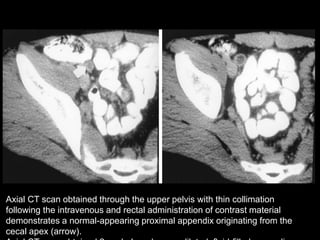

Axial CT scan obtained through the upper pelvis with thin collimation

following the intravenous and rectal administration of contrast material

demonstrates a normal-appearing proximal appendix originating from the

cecal apex (arrow).

Axial CT scanobtained through the upper pelvis with thin collimation following the intravenous and rectal administration of contrast material demonstrates a normal-appearing proximal appendix originating from the cecal apex (arrow).